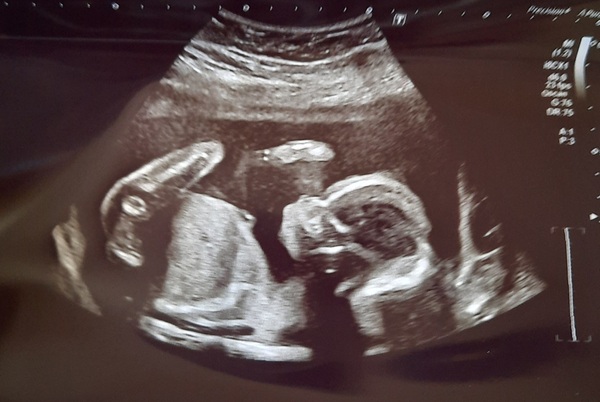

Hi all! Thanks for the good wishes! Pleased to report my son is fine, just had my 20 week scan. He was wriggling so much though that the sonographer couldn't fully catch the heart and diaphragm measurements so she's bringing me in again for a rescan in 2 weeks' time. I had to jump, roll, empty my bladder and he still had his leg and elbow over his chest 🙈🙈🙈 Nevermind. She said she didn't see anything concerning luckily so hopefully all will be ok at the rescan.

He is moving loads today, don't think he enjoyed so much pressure lol, the scan took 40 mins!

Beautiful scan @PurplePansy05 - a wiggly baby is a good baby!